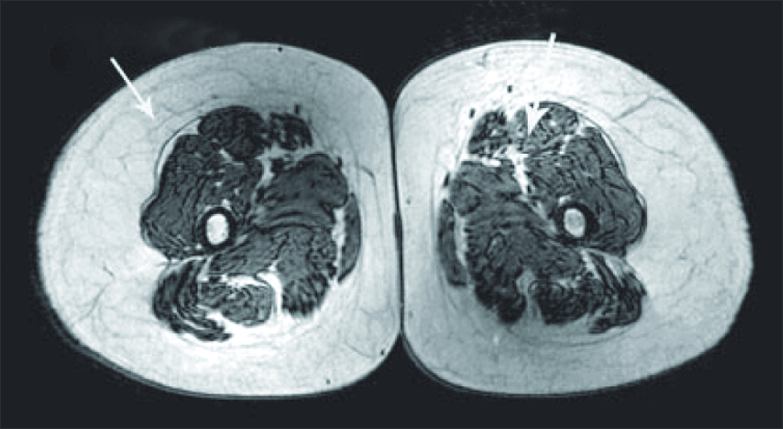

Sarcopenia, defined as age-related, involuntary loss of muscle mass and strength, is inevitable but ONLY if you do not takes steps to counteract it. These incredible MRI images show a cross section of a thigh of a 70 year old man who has done no strength exercise and allowed nature to take its course. The one on the right is a triathlete of the same age. There was a third image that I haven’t featured which compared the 70 year old with a 40 year old triathlete – there was very little difference.

Studies have shown that it is more than possible to build muscle whatever your age, and the good news is, the changes can happen relatively quickly.